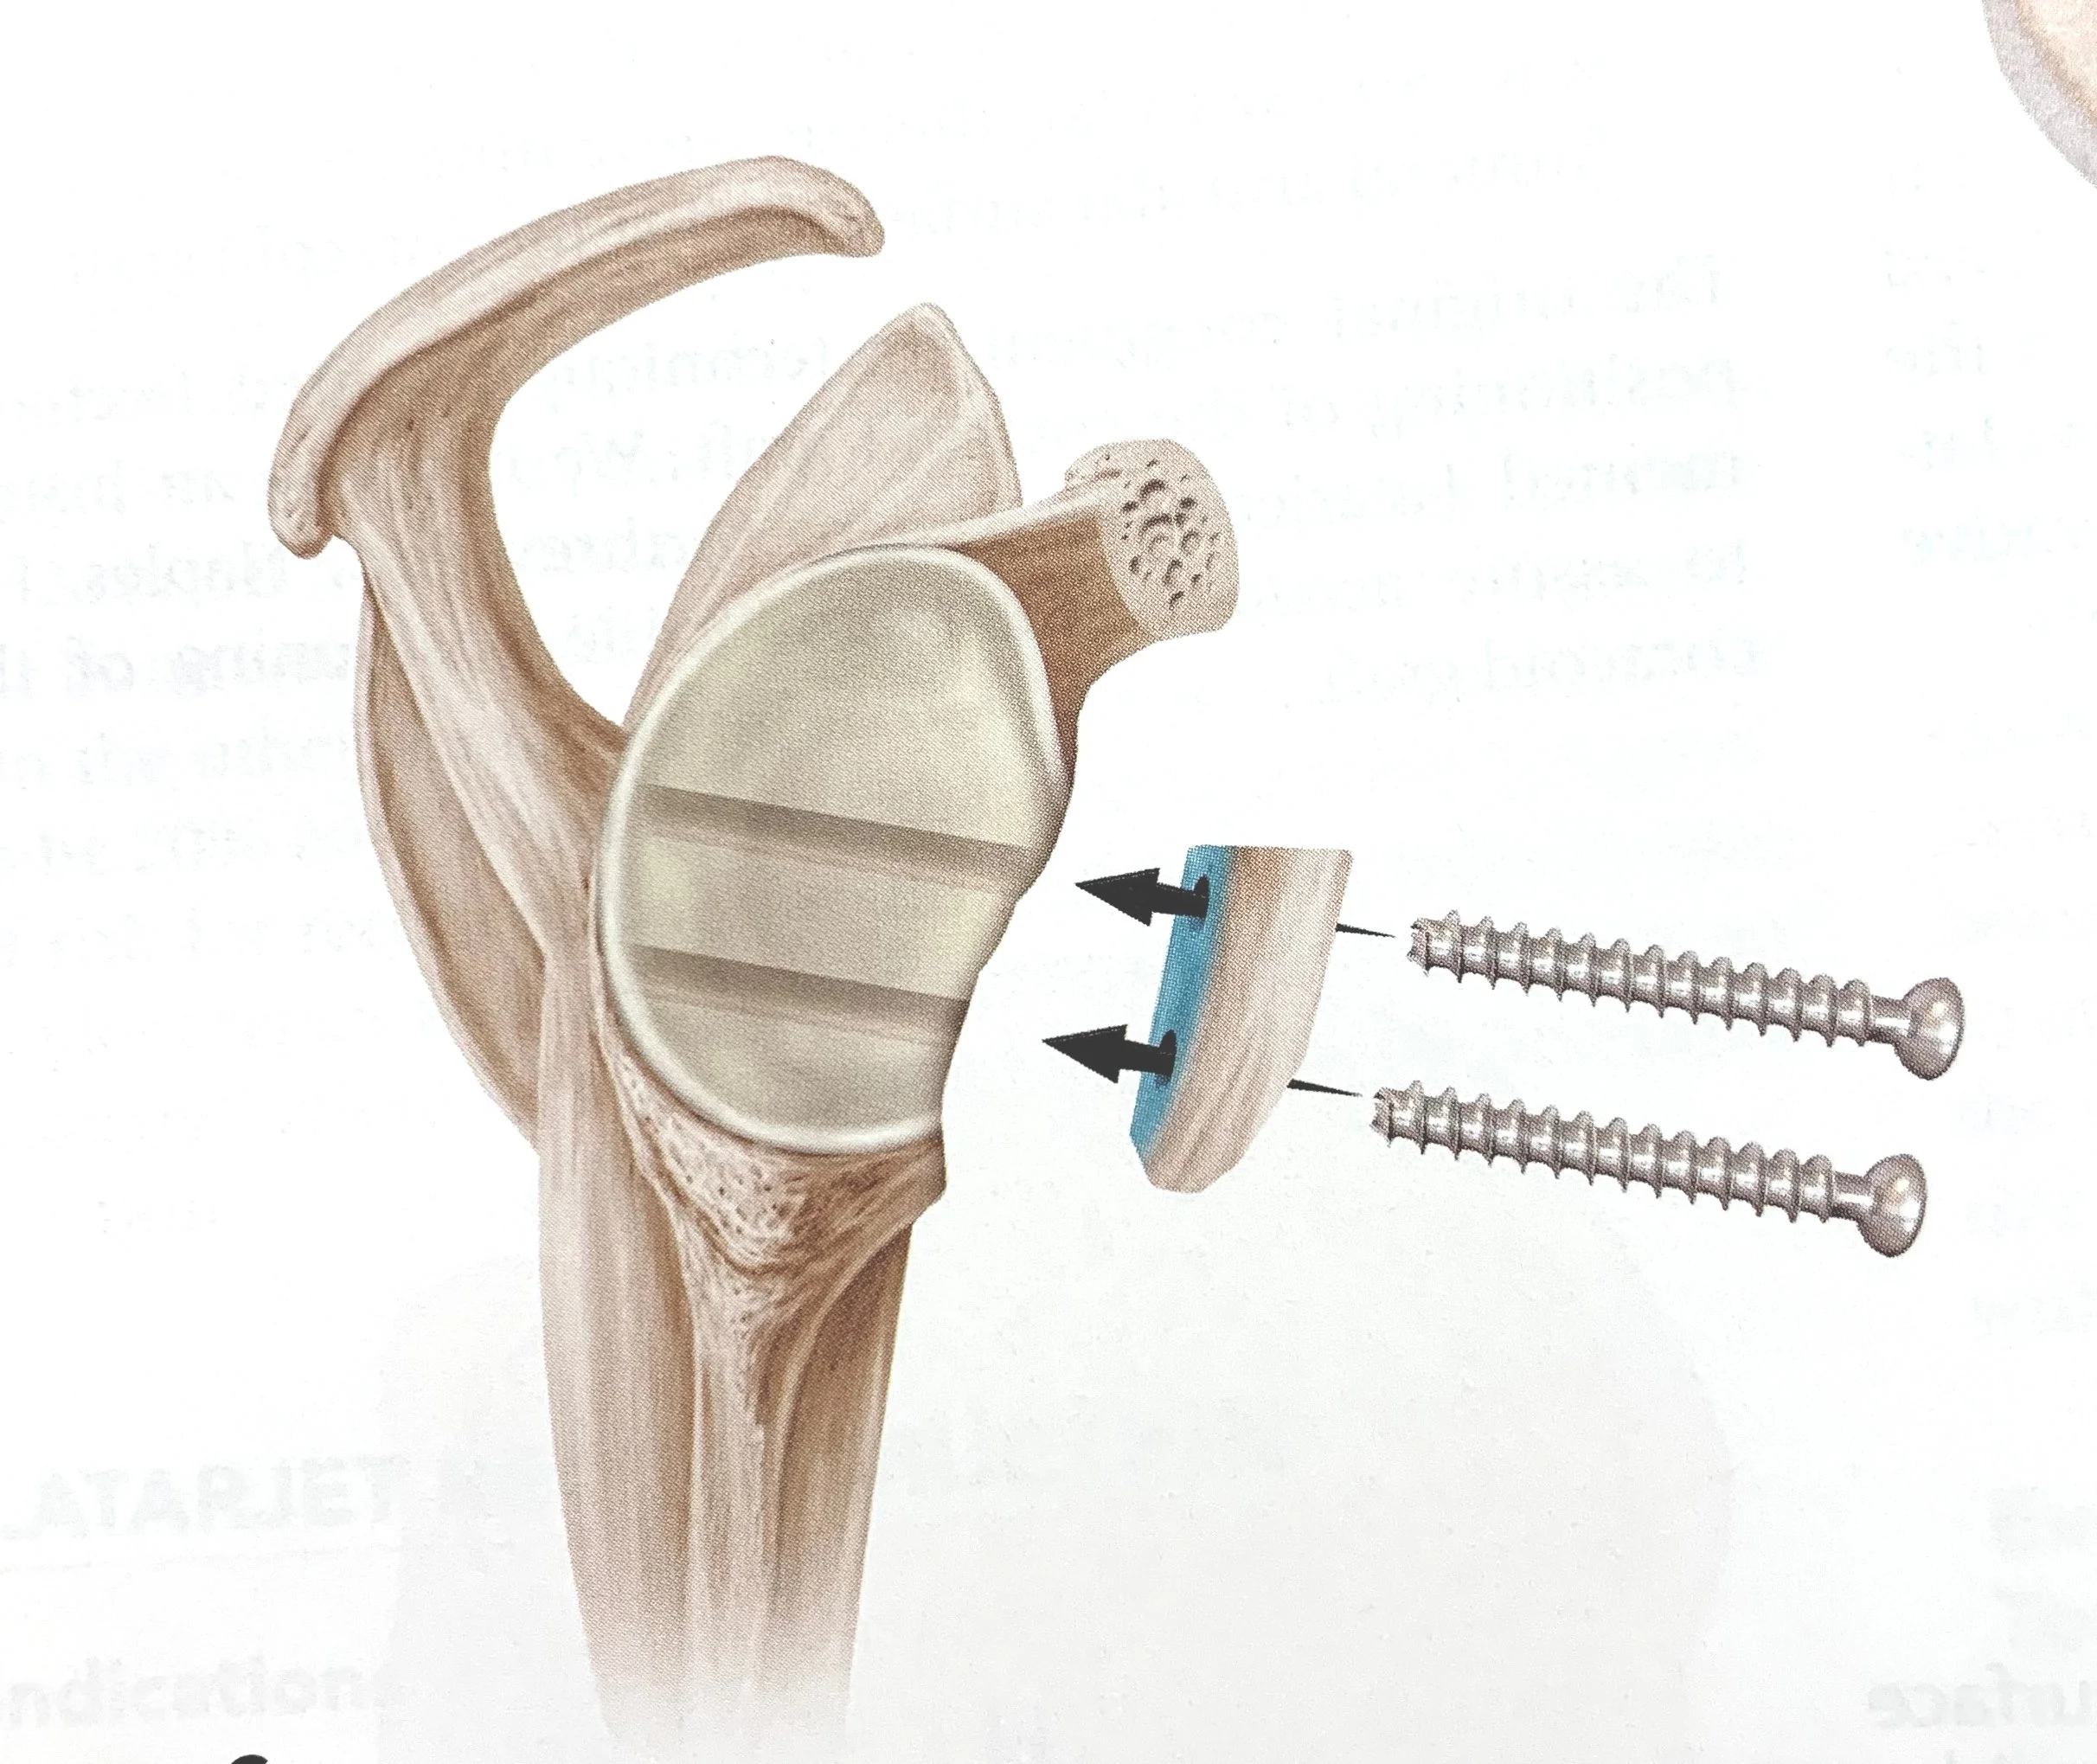

Operatie: Latarjet Procedure

Enige tijd geleden onderging ik een Latarjet-procedure aan mijn schouder. Na meerdere subluxaties en ontwrichtingen in het verleden gaf mijn arts mij een duidelijke keuze: óf een operatie ondergaan, óf mijn sportactiviteiten sterk verminderen. Aangezien ik 31 ben en enorm gepassioneerd ben door sport, voelde de beslissing vrij vanzelfsprekend.